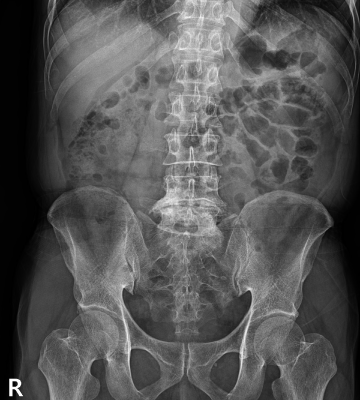

척추분리증 수술 전·후

2022.11.28

ㆍ환자 동의를 받은 자료이며, 이미지 사진은 실물과 다를 수 있습니다.

ㆍ모든 자료는 새움병원 자료입니다.